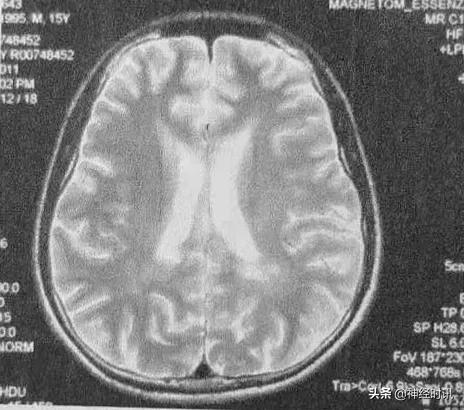

头部MRI(2011年5月):左侧半卵圆区、双侧侧脑室角及体旁白质、左侧额叶颞叶皮质下、右侧脑干缘可见斑片状及斑点状常T2信号影,无强化。

临床诊断上,除了McDonald2010年诊断标准(现已更新至McDonald2017年诊断标准)外,MRI也具有十分重要的重要。结合上述病例,该患者头部MRI中有多发的白质部分病灶,颈部MRI中可见单个椭圆形病灶,边界清楚。